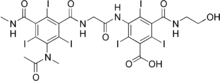

Ioxaglic acid

| Formula | C24H21I6N5O8 |

Ioxaglic acid (trade name Hexabrix) is an iodine containing molecule used as a low-osmolality contrast medium.[1]